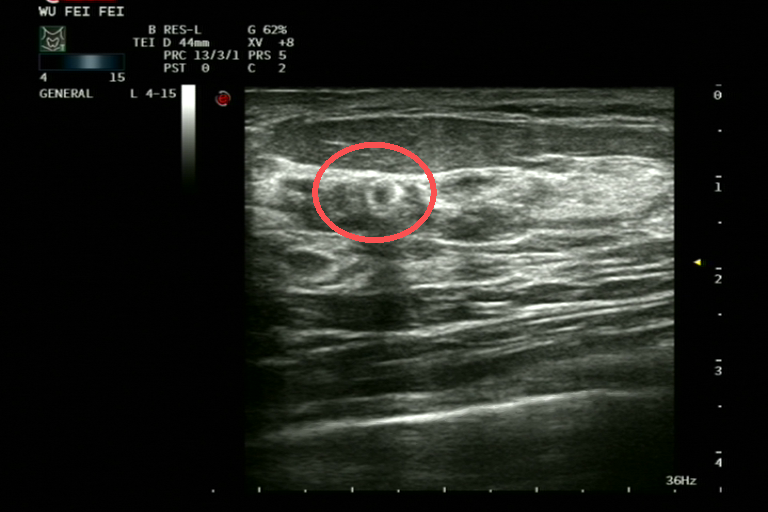

▲ 宗方主任医师、郝静主任医师正在评估病灶位置

“最关键的是,即使肿瘤经过化疗、内分泌治疗后明显缩小甚至临床‘消失’,标记夹依然能准确‘指路’。”

郝静表示,定位夹可以帮助外科医生在术中快速找到原始病灶部位,既能保证肿瘤完整切除,又能最大程度保留正常乳腺组织,对年轻女性患者尤为重要,这是真正意义上的精准乳腺外科